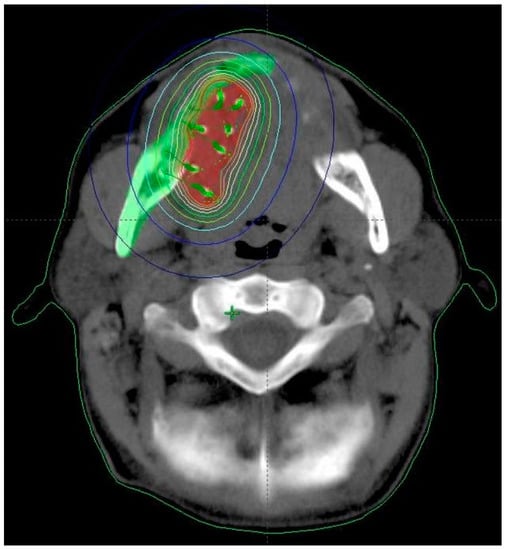

- Kovács, G.; Martinez-Monge, R.; Budrukkar, A.; Guinot, J.L.; Johansson, B.; Strnad, V.; Skowronek, J.; Rovirosa, A.; Siebert, F.A.; GEC-ESTRO Head & Neck Working Group. GEC-ESTRO ACROP recommendations for head & neck brachytherapy in squamous cell carcinomas: 1st update—Improvement by cross sectional imaging based treatment planning and stepping source technology. Radiother. Oncol. 2017, 122, 248–254. [Google Scholar] [CrossRef] [PubMed]